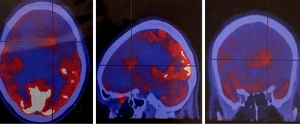

Somatostatin is a neuropeptide released by endocrine cells, neurons, and immune cells which its functions include neuroregulation (sensory, motor, and cognition) and cell growth inhibition by paracrine and autocrine pathways (37,38). Somatostatin works through a group of transmembrane G protein-coupled receptors that enter the cell following binding to specific ligands (39). So far, six subtypes of somatostatin receptors (SSTRs) are discovered including SSTR 1, 2A, 2B, 3, 4, and 5. A broad spectrum of brain tumors express different subtypes of SSTR on their surface including frequent primary brain tumors e.g., gliomas and meningiomas, pediatric brain tumors (medulloblastomas), pituitary adenomas, and supratentorial primitive neuroendocrine tumors (PNETs) (40-43). Dutour and colleague (44) have shown that gliomas and meningiomas, as the first and second most common primary brain tumors, are positive for different subtypes of SSTR. It was demonstrated that although all of them have at least one SSTR subtype, many of these harboring multiple SSTR subtypes. They provided proofs on detecting SSTRs in both tumors and their surrounding tissues, particularly blood vessels. Concerning gliomas, low-grade gliomas (WHO grade I, II) depicted higher expression levels compared to high-grade gliomas (WHO grade III, IV) (45). To date, three 68Ga-DOTA peptides are developed for clinical imaging comprised of 68Ga-DOTA-TOC, 68Ga-DOTA-NOC, and 68Ga-DOTA-TATE. The shared property of these 68Ga-DOTA peptides is the ability in binding to SSTR2, and they differ with regard to their SSTR subtype affinity and profile (Figures 4,5).

Meningioma is the second most frequent primary brain tumor and is benign in 90% of cases. The current standard imaging modality in diagnosis is conventional MR imaging (43). Although the SSTR receptors are positive in the healthy leptomeningeal cell, the meningioma cells express higher levels of them (46,47). Afshar-Oromieh et al. (48) aimed to compare the ability in detecting meningioma lesions between 68Ga-DOTA-peptide PET/CT and contrast-enhanced MRI (CE-MRI) within a total of 134 patient. They revealed that 68Ga-68Ga-DOTA-peptide PET/CT has higher accuracy compared to CE-MRI in meningioma detection (190 vs. 171). The investigators concluded that 68Ga-DOTA-peptide PET/CT could play a complementary role with MRI in cases where MRI finding has failed in definitive diagnosis or lake of feasibility for biopsy. Another promising potential of 68Ga-DOTA-peptide PET/CT was reported by Milker-Zabel and colleagues (49) through a study that showed target volume delineation using 68Ga-DOTA-PET/CT and MRI in comparison to CT or MRI alone has changed the radiotherapy planning in 73% of 26 patients. Gehler et al. (50) reported similar results as well. One example of this modality in meningioma is illustrated in Figure 6.